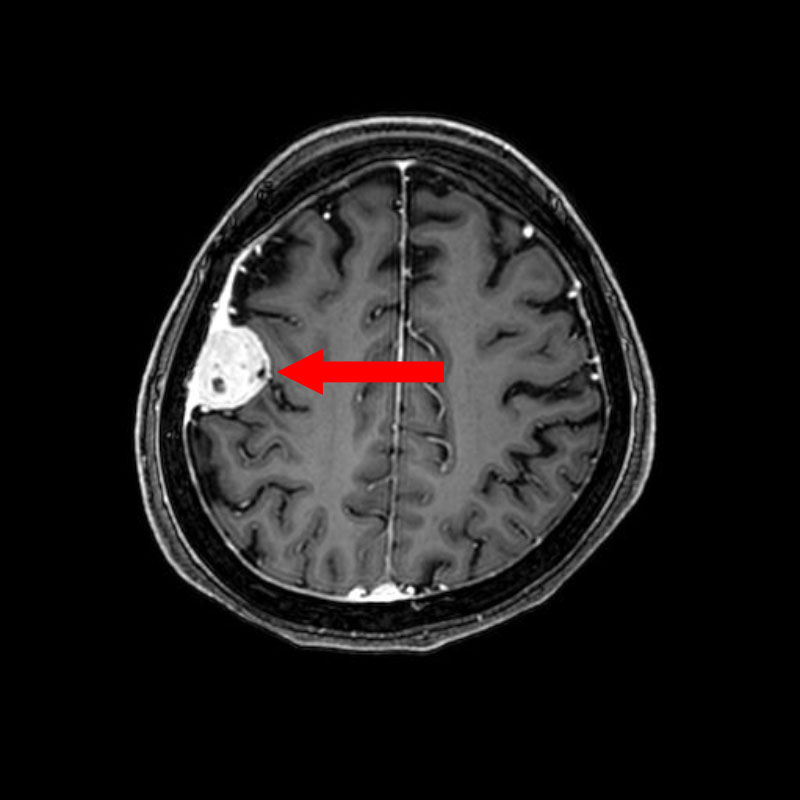

No.’25_108 手術前1

No.’25_108 手術前2